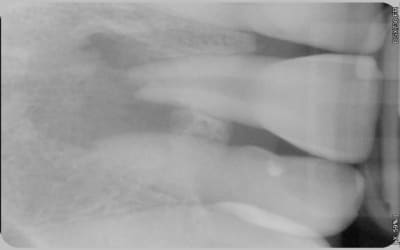

Suite à un choc, un patient présente un kyste important et une résorption externe de la 11. L'apex est complétement ouvert. La table osseuse vestibulaire a disparu.

Voici les photos.

Comme vous pouvez le voir la lésion est très importante. Pensez-vous que cette dent ai une chance? Mon maître de stage lui laissait 40% de chance, je n'ai pas de recul mais ça me semble beaucoup. J'ai preferé dire au patient que ça serrait délicat car il n'imaginait même pas la possibilité d'enlever la dent.

Pour la résection apicale, j'y avais penser mais la racine me semble déjà bien courte.

J'ai prévenu le patient de la perte osseuse et donc des difficultés posées pour une pose d'implant.

je précise qu'en vestibulaire, il y a une voussure, c'est dépressible ce qui me premet de penser à la perte de la table osseuse externe